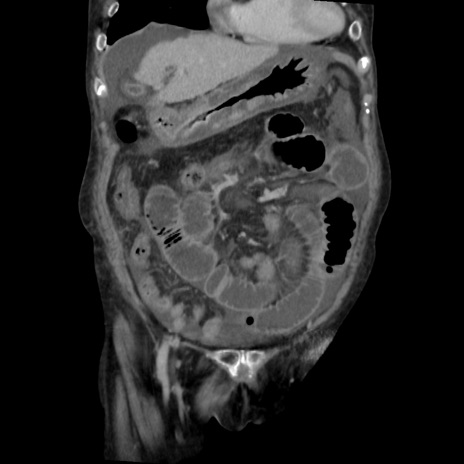

症例31(冠状断像)

矢状断像